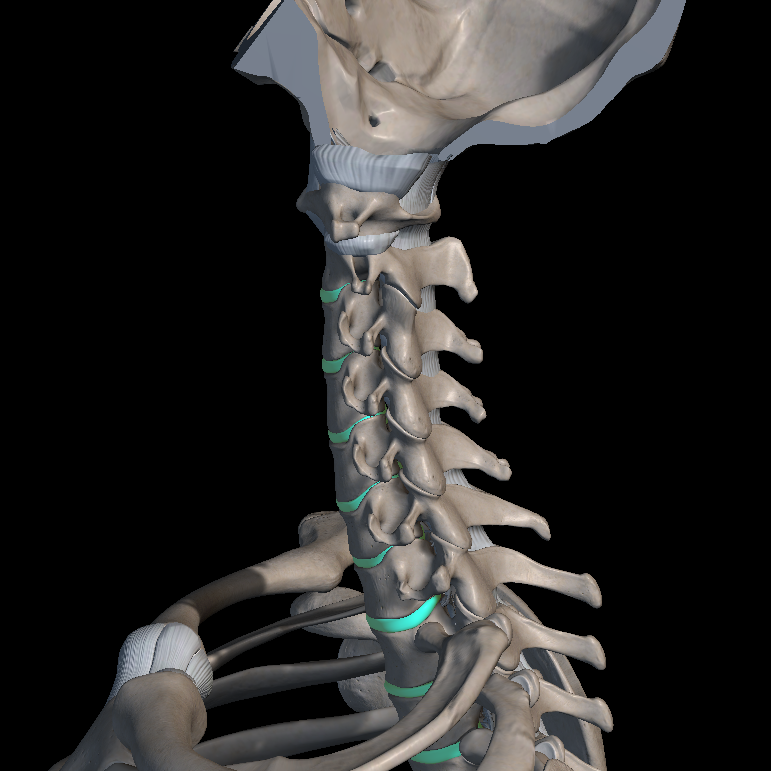

목디스크란?

목디스크라는 질환은 디스크(추간판)이라는 척추뼈 사이사이에 위치한 디스크가 변형되면서 경추 신경을 압박하거나 자극하여 목의 통증, 두통, 팔 저림 현상을 일으키는 질환입니다.

일반적으로 목디스크는 노화로 인해 디스크가 탄성을 잃게 되면서 발생하게 되는데요. 특히나 비만, 잘못된 자세, 스트레스, 잘못된 운동으로 인해 발생하는 경우들이 많습니다.

목디스크는 허리디스크와 동일한 메커니즘으로 발생하는 척추 신경 질환 중 하나이며, 규칙적인 운동과 올바른 치료가 병행된다면 충분히 개선할 수 있는 질환입니다.